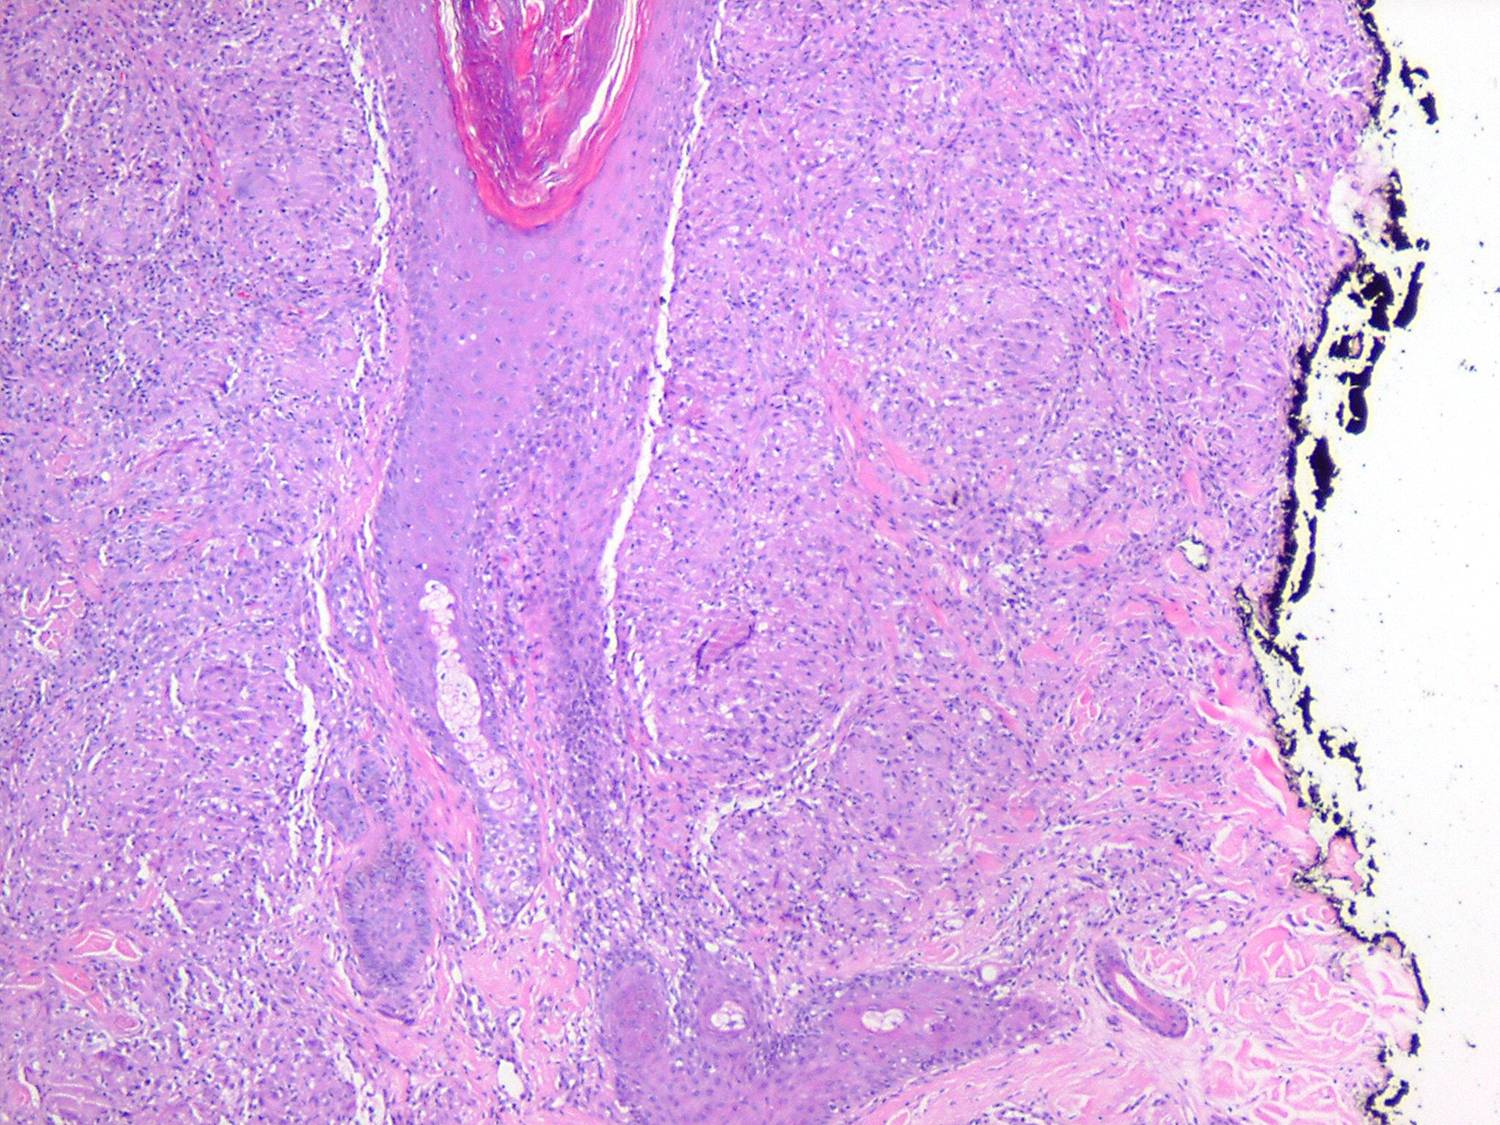

Like lesions in other organs, the cutaneous lesions of chronic, persistent sarcoidosis are characterized by the presence of circumscribed collections of epithelioid histiocytes-so-called epithelioid cell tubercles-which show little or no necrosis .

The papules, plaques, and lupus pernio-type lesions show variously sized aggregates of epithelioid cells scattered irregularly through the dermis with occasional extension into the subcutis (. In the erythrodermic form, the infiltrate shows small granulomas in the upper dermis intermingled with numerous lymphocytes

and, rarely, also giant cells . Typical sarcoidal granulomas are found in the ichthyosiform lesions , in ulcerated areas , and in atrophic lesions . Verrucous sarcoid exhibits prominent associated acanthosis and hyperkeratosis . Biopsies of

hypopigmented sarcoid may reveal granulomas, which may have a perineural component or fail to reveal granulomas . In subcutaneous nodules, larger epithelioid cell tubercles lie in the subcutaneous fat .

In typical cutaneous lesions of sarcoidosis, the well-demarcated islands of epithelioid cells contain few, if any, giant cells. Those that are present are usually of the Langhans type. A moderate number of giant cells can be found in old lesions. These giant cells may be large and irregular in shape. In a minority of cases, giant cells contain asteroid bodies or Schaumann bodies . Asteroid bodies , which are more common, are star-shaped eosinophilic structures that, when stained with phosphotungstic acid-hematoxylin, produce a center that is brown-red with radiating blue spikes . Schaumann bodies are round or oval, laminated, and calcified, especially at their periphery. They stain dark blue because of the presence of calcium. Neither of these two bodies is specific for sarcoidosis: They have been observed in a variety of other granulomas, including those of leprosy, tuberculosis, foreign-body reactions, and necrobiotic xanthogranuloma .

Tuberculoid leprosy, which may show granulomas in association with only a sparse lymphocytic infiltrate, can also be difficult to distinguish from sarcoidosis. Only 7% of cases of tuberculoid leprosy show acid-fast bacilli, and then only a few, so that they may easily be overlooked . The most likely place to find bacilli is within degenerated dermal nerves (the granulomas of tuberculoid leprosy form around dermal nerves that are undergoing necrosis). The granulomas of tuberculoid leprosy show small areas of central necrosis more often than those of sarcoidosis. In addition, the granulomas of tuberculoid leprosy, in contrast with those of sarcoidosis, follow nerves and therefore often appear elongated . Clinical correlation may be required to distinguish between these two diseases. For example, in the United States, leprosy virtually can be excluded if a patient has not been in an endemic area (either in a foreign country or where it is carried in armadillos domestically, e.g., Texas and Louisiana) or has not had prolonged close contact with another individual with the disease